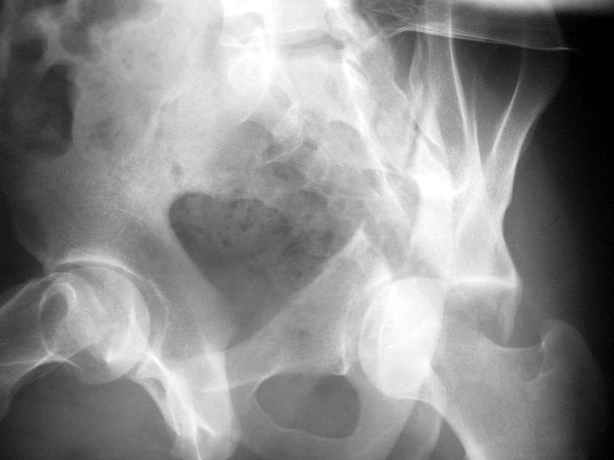

Высылаю пример еще одного случая, остеосинтез пластиной из подвздошного доступа.